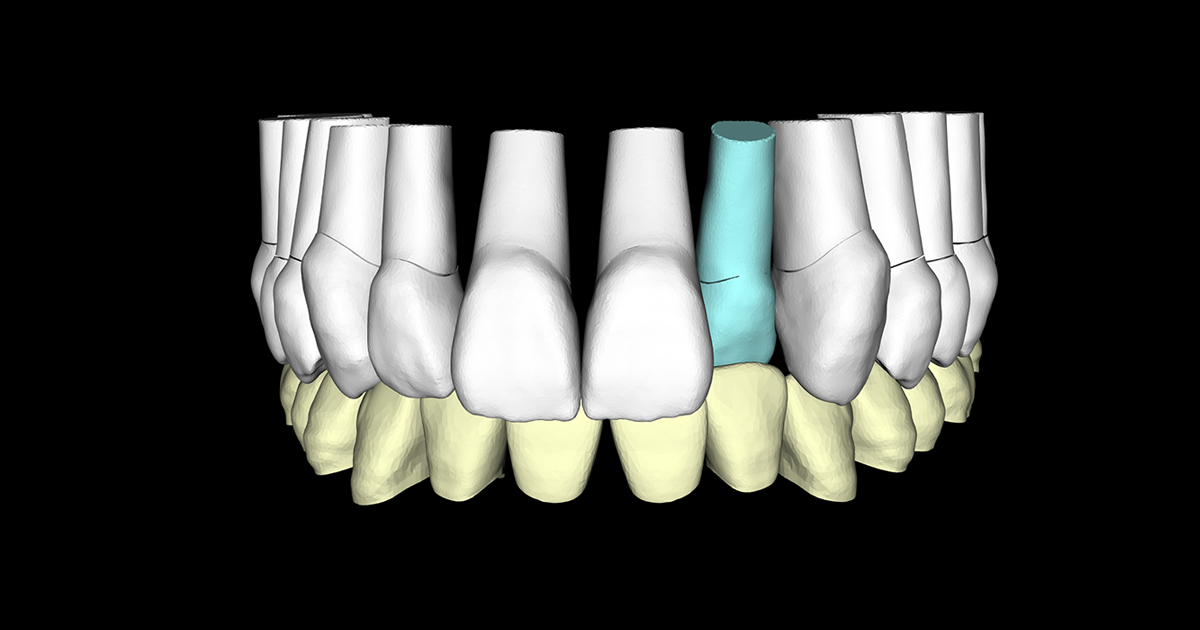

アンカースクリューによる圧下矯正と歯冠を歯肉下までスライスして前方傾斜移動

支台歯(修復前の形成歯)が対合前歯の前方に位置したら仮歯を装着し矯正は完了